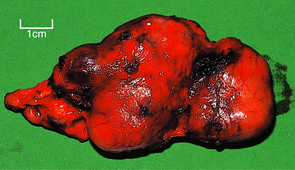

Acute insufficiency

Acute insufficiency (‘adrenal apoplexy’) was first noted in children by Waterhouse and Friderichsen who, in 1911 and 1918 respectively, independently described acute haemorrhagic necrosis of the adrenals in the course of meningococcal septicaemia. Other acute septicaemias, especially those due to Gram-negative bacteria, may cause a similar effect. The adrenal cortices are necrotic and the medullae contain acute haemorrhage (Fig. 17.18). The adrenal necrosis is probably due to disseminated intravascular coagulation (DIC). The symptoms are attributable to lack of mineralocorticoids (salt and water loss with hypovolaemic shock) and of glucocorticoids (failure of gluconeogenesis resulting in hypoglycaemia).

Fig. 17.18 Adrenals in Waterhouse–Friderichsen syndrome. The adrenals from a child dying from meningococcal septicaemia are destroyed by haemorrhage.